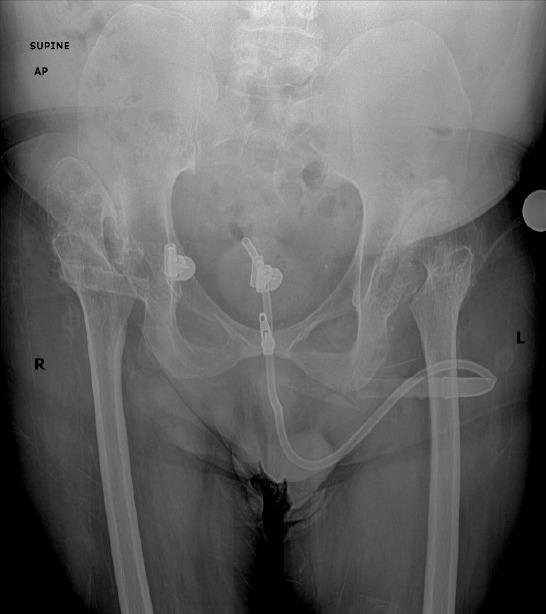

A 47-year-old man presented with bilateral hip and knee pain. Radiographs demonstrated valgus knee deformities with severe arthrosis and bilateral femoral head subluxation. The patient had a history of spina bifida with chronic lower extremity weakness and neurogenic bladder. He underwent staged bilateral instrumented knee arthrodesis and staged bilateral total hip arthroplasty (THA).

一名47岁男性因双侧髋部和膝部疼痛就诊。X线片显示膝外翻畸形伴严重关节炎和双侧股骨头半脱位。该患者有脊柱裂病史,伴有慢性下肢无力和神经源性膀胱。他接受了分期双侧器械辅助膝关节融合术和分期双侧全髋关节置换术(THA)。